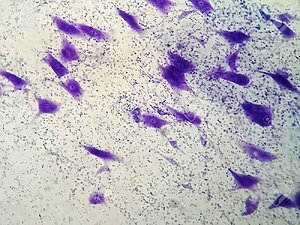

Después hemos podido ver a través del microscopio algunas muestras, asar de la maqueta (lo que imaginamos) al microscopio (lo que vemos de verdad) lo ha convertido en una gran experiencia.🔬. Nuestra clase se ha transformado en un laboratorio científico.

Después de la teoría, ¡pasamos a la acción! Pudimos observar varias muestras reales a través del microscopio, fue un momento mágico: ver con sus propios ojos aquello que es invisible.

Fue emocionante descubrir que esas estructuras que Marco dibujó en sus cartulinas están ahí de verdad.

Células del cerebro: ¡Lo más impresionante! Vimos cómo son por dentro las células que nos ayudan a pensar y sentir.